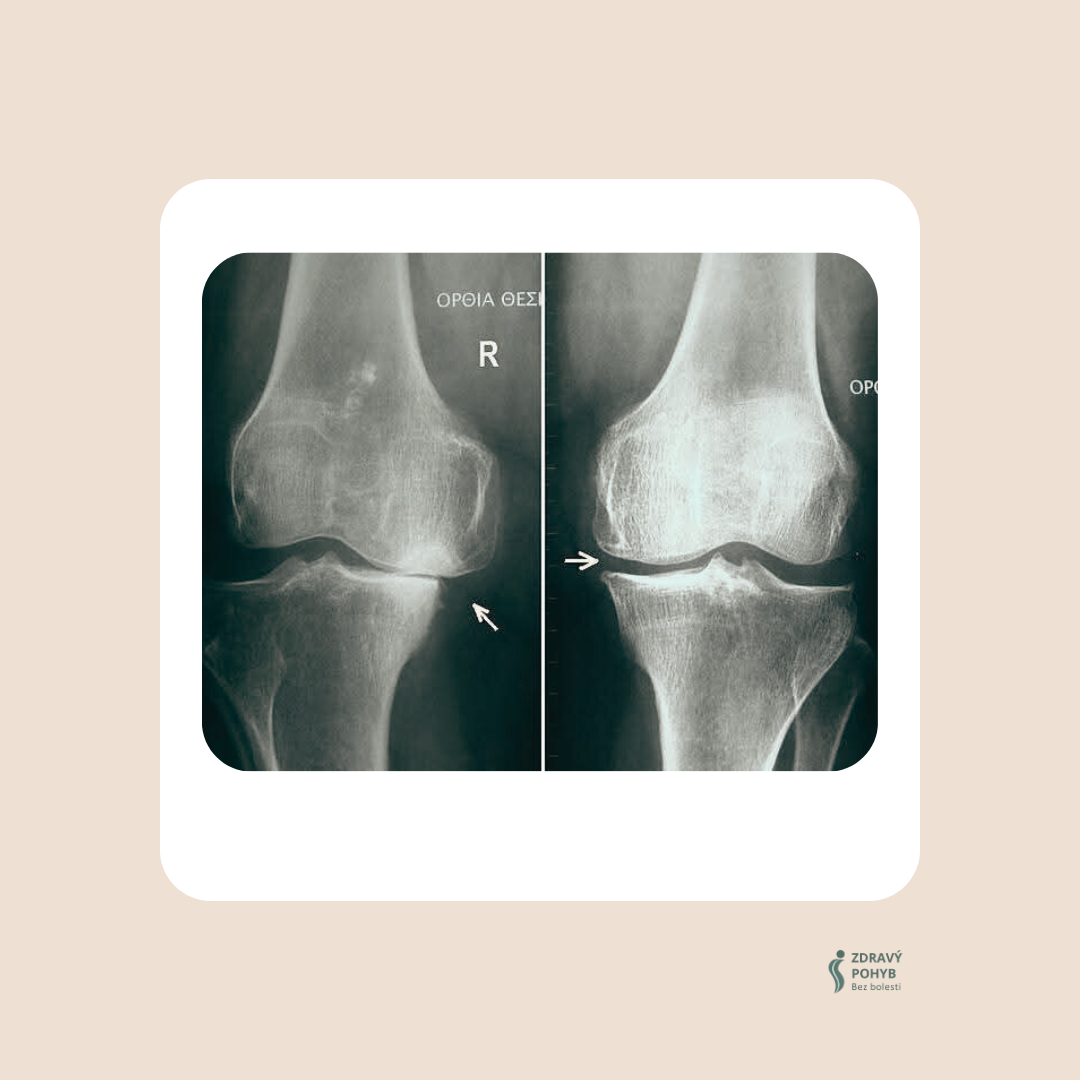

👀 Když se podíváte na rentgen, vidíte důsledek.

Kosti v koleni se téměř dotýkají, prostor pro chrupavku mizí.

Ale tohle není začátek problému – tohle je důsledek, finální fáze.